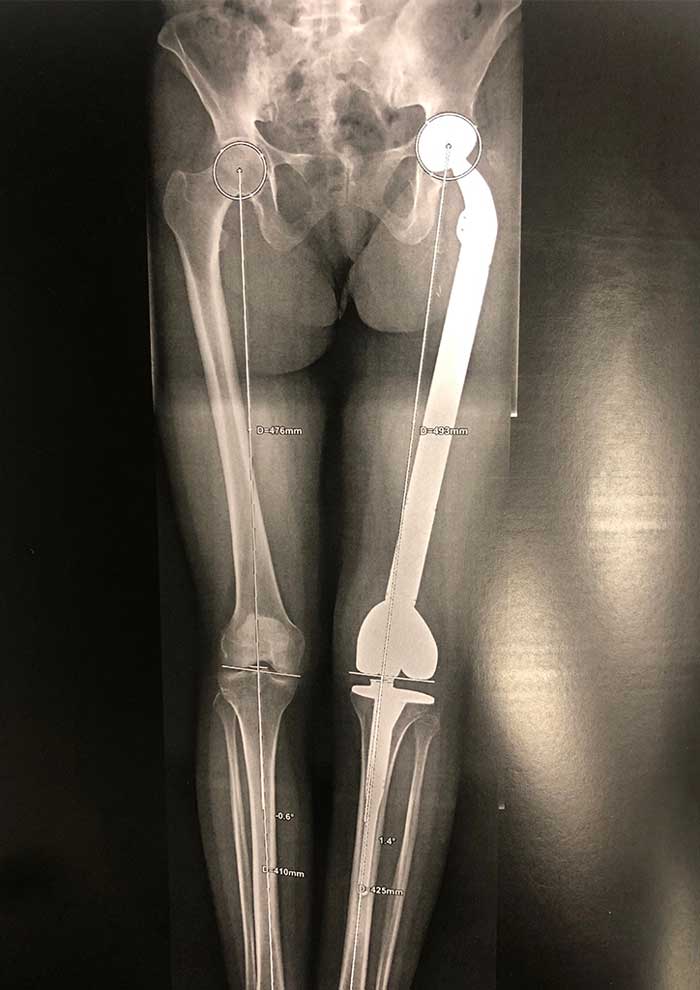

Dès 2006, il a démontré la possibilité de réaliser simultanément deux prothèses de hanche sur le même patient (références 23 à 28), stratégie qui est désormais utilisée par le Docteur Jean-Luc Raynier, et il a mis en évidence les limites des cupules de resurfaçage de hanche (référence 29). Il est également spécialiste de la reconstruction osseuse par Ingénierie tissulaire, sujet de sa thèse de science, objet de nombreuses publications internationales depuis 2005 (références 30 à 36). Enfin, le Professeur Trojani est spécialisé dans les interventions exceptionnelles en chirurgie tumorale, au niveau du genou et du bassin (Figures 3 à 5).

Figure 3 : chirurgie de résection complète du fémur avec mise en place d’une prothèse de fémur total, c’est-à-dire simultanément d’une prothèse de hanche et d’une prothèse de genou, du fait d’une tumeur osseuse atteignant tout le fémur (Sarcome d’Ewing).